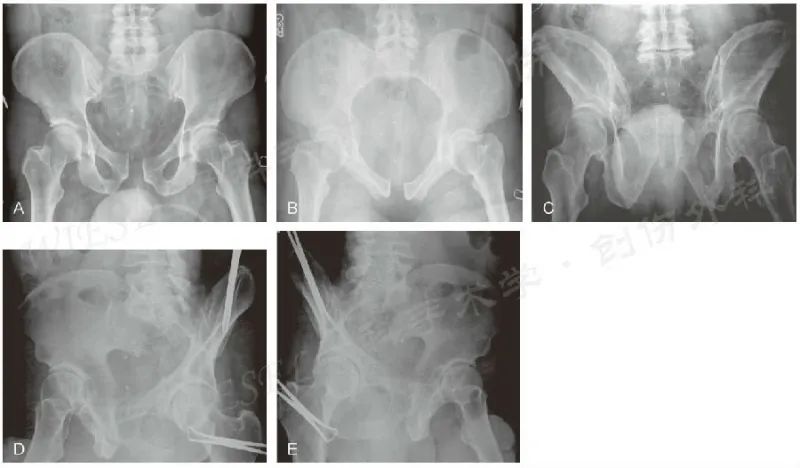

骨盆放射学检查包括前后位、入口位、出口位和Judet位(图5)。

图5 A~E.一例骨盆创伤、耻骨联合增宽患者的骨盆前后位(A)、入口位(B)、出口位(C)以及Judet位(D、E)影像(经允许引自Jodi Siegel, MD&David Templeman, MD)